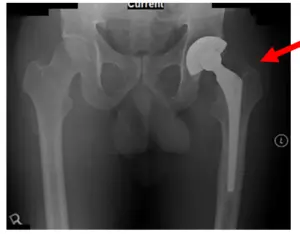

Patient is a 70 year old male who came in with severe left hip pain after having a left Total Hip Arthroplasty (THA) done several years ago. On initial visit with us, X-Rays showed findings of periprostheticlucency/osteolysis of the femoral stem and mild thickening of the distal cortex. Loosening of the prosthesis is also seen, along with pedestal at the distal end. X-rays are shown below.

X-Rays of the Left Hip Pre-Operative of Left Revision THA in September 2011